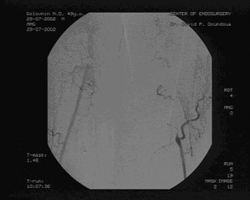

При ангиографии выявлено: субтотальный стеноз правой общей подвздошной артерии (ОПА) в дистальном отделе, бифуркационный стеноз правой общей бедренной (ОБА) артерии 70%, окклюзия правой ПБА в Гунтеровом канале длиной 4 см, окклюзия левой ПБА от устья до подколенной артерии, подколенные артерии и артерии голени проходимы, без гемодинамически значимых сужений. (см. рис. 2)

Рис. 2. Результаты до операционного ангиографического исследования.